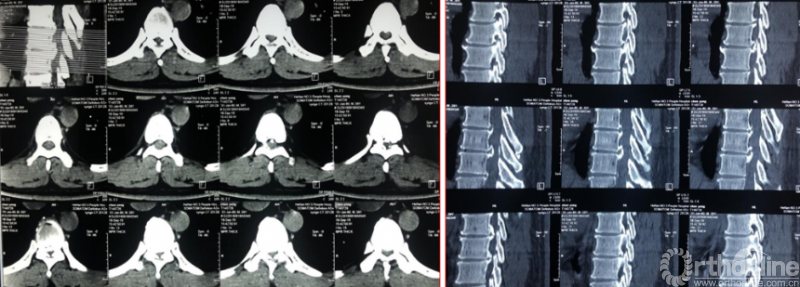

术前资料